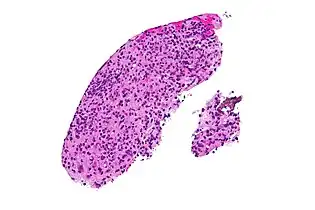

Real-time PCR is useful in pathogen detection, gene expression and regulation, and allelic discrimination. This PCR technique utilizes the 5' nuclease activity of Taq DNA polymerase to cleave a nonextendible, fluorescence-labeled hybridization probe during the extension phase of PCR.[63] A second fluorescent dye, e.g., 6-carboxy-tetramethyl-rhodamine, quenches the fluorescence of the intact probe.[63] The nuclease cleavage of the hybridization probe during the PCR releases the effect of quenching resulting in an increase of fluorescence proportional to the amount of PCR product, which can be monitored by a sequence detector.[63] Lymph nodes affected by Toxoplasma have characteristic changes, including poorly demarcated reactive germinal centers, and scattered epithelioid histiocytes.[64]

Micrograph of a lymph node showing the characteristic changes of toxoplasmosis (scattered epithelioid histiocytes (pale cells), monocytoid cells (top-center of image), large germinal centers (left of image)) H&E stain